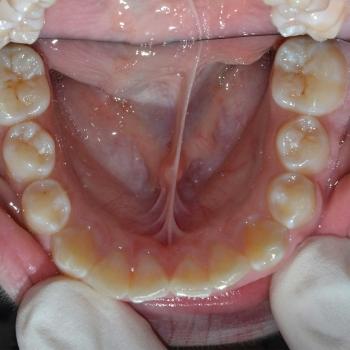

Gergő és édesanyja fogorvosi javaslatra keresett fel, a bal felső 2. kisőrlő hibás pozíciója miatt. A konzultáció során egyértelművé vált, hogy az előbb említett fog helyét teljes mértékben elfoglalták az előtte, illetve mögötte elhelyezkedő fogak, gyakorlatilag 0mm helyet hagyva a probléma megoldására. Ilyen esetekben felmerül a szájpadi irányba kiszorult fog eltávolítása, de a felső fogívben tapasztalható résesség a helyteremtés mellett szólt.

A kezelés első lépéseként Frog készülékkel hátrafelé mozdítottuk a bal felső első nagyőrlőt, ezzel elrendezve a nagyőrlők érintkezését, másfelől 4mm helyet teremtve a második kisőrlő számára. Ez a hely még nem volt elegendő, így rögzített fogszabályozóval zártuk a nagymetszők közötti, illetve az első kisőrlő előtti rést, mellyel további 2.5mm helyet nyertünk. Az így már 6.5mm-es rés elegendő volt ahhoz, hogy a kiszorult kisőrlőt bemozdítsuk a kívánt pozícióba, ezzel kialakítva egy funkcionálisan megfelelő és esztétikus felső fogívet. Mivel a harapás korrekciója, azaz a funkció helyreállítása kizárólag a felső fogív kezelésével is kivitelezhető volt, így a szülők nem kérték az alsó fogív torlódásának a megoldását.

A kezelés teljes időtartama: 2 év